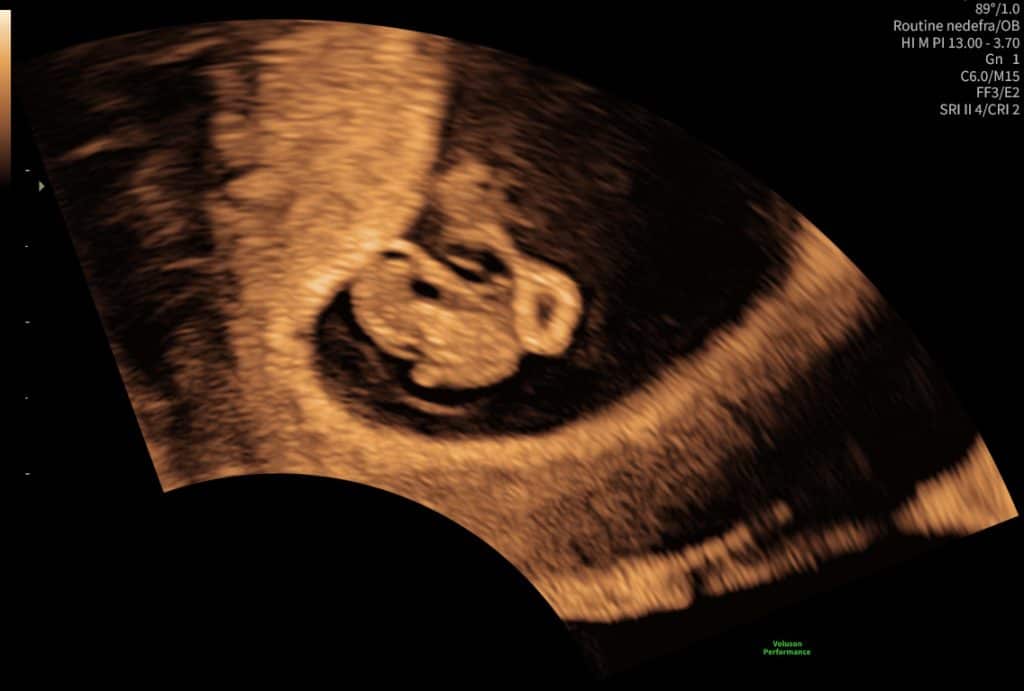

Ultralydsscanning uge 10 foster med hoved og krop

Ultralydsscanning uge 9 foster

Ultralyd i uge 9–10. Fosteret er mere tydeligt, men detaljer kan stadig variere.

I denne periode er der flere bevægelser som ofte ses tydeligere på video end på stillbilleder.

Kort ultralydssekvens fra uge 10 hvor foster kan ses i profil med hjerte som slår. Meget livlig